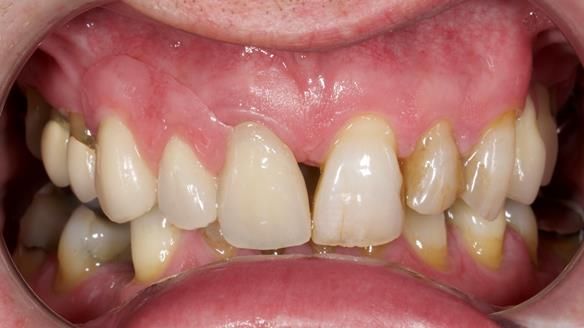

Welcome to Newsletter 67, where I will detail the making and fitting of an upper metal-based partial denture/splint (“Combat denture”) for Brian, a patient with a powerful locked occlusion and deep overbite. The full protocol workflow is presented here.

- Bruxism: The upper and lower teeth are worn and chipped due to heavy clenching and grinding. With a powerful bite and limited space for replacement teeth, dental implants supported fixed teeth are not recommended. A simpler solution is a metal-based partial denture/splint (“Combat denture”) as planned below. This will act as a splint to protect and replace the missing teeth.

- Restored Teeth: The remaining upper teeth and lower back teeth have large fillings and crowns, making them structurally weak. The new denture will reduce the forces on these teeth to help them last longer, though they may still require new restorations or extractions occasionally.